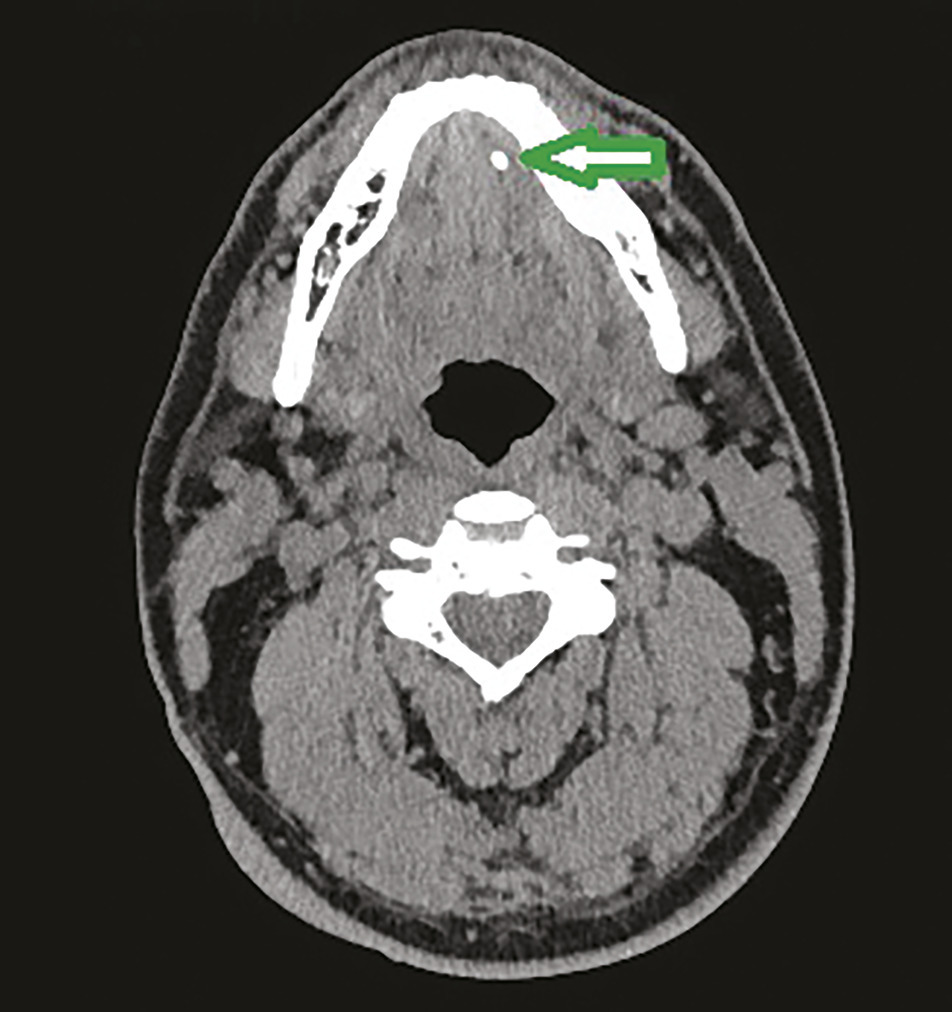

Scanner, une excellente sensibilité

Le scanner peut être réalisé sans injection de produit de contraste dans la majorité des cas (l’injection de produit de contraste peut s’avérer utile en cas d’atteinte inflammatoire de la glande ou de recherche d’abcès). Il a une sensibilité de 100 % et une spécificité de 75 %. Il permet au chirurgien une bonne localisation de la lithiase et est un examen relativement facile à obtenir (fig. 1 ).6 Il comporte cependant quelques inconvénients : il s’agit d’un examen irradiant, et il peut être difficilement interprétable en cas d’artéfacts dentaires.